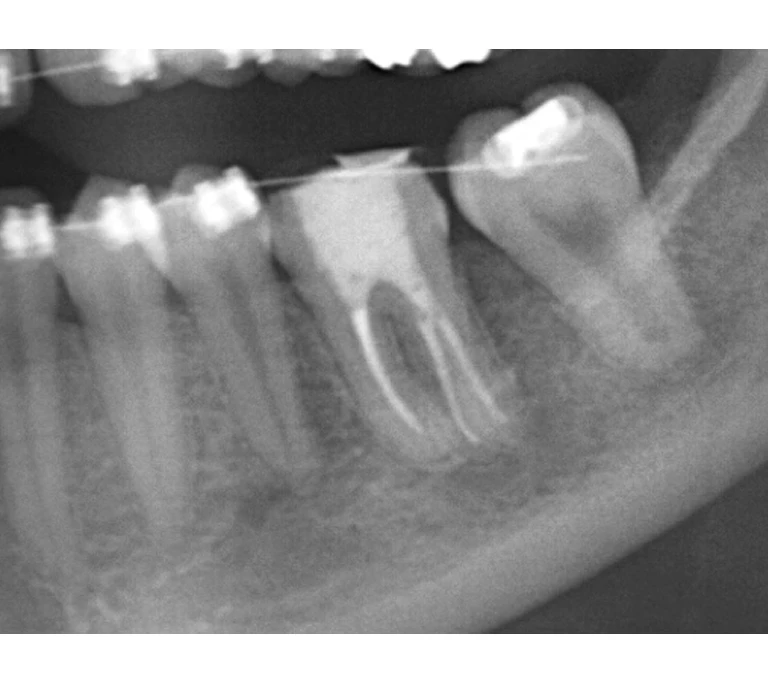

case 3.

治療前

治療後

| 主訴 | 左下奥歯が痛い、歯ぐきの腫れ。 前医で抜歯を提案されたがセカンドオピニオン希望でご来院。 |

|---|---|

| 治療期間 | 約半年(6か月) |

| 治療費 | 約5万円 |

| 治療内容 | 前医ではラバーダム不使用であったため、ラバーダム、マイクロスコープ下にて根管治療を施術。 痛みは消失したが腫れは治らなかったため、意図的再植を行い腫れは消失した。治療後のレントゲンは意図的再植後3年経過したもの。 |

| 治療のリスク | マイクロスコープやCTを使用し、可能な限り精密な根管治療を行っていますが、歯根の形態や病変の大きさ、過去の治療履歴などにより、治癒が得られない場合があります。 また、治療後に再感染や歯根破折が生じることもあり、その場合は再治療や抜歯が必要となることがあります。 治療結果には個人差があり、すべての症例で同様の経過を保証するものではありません。 |